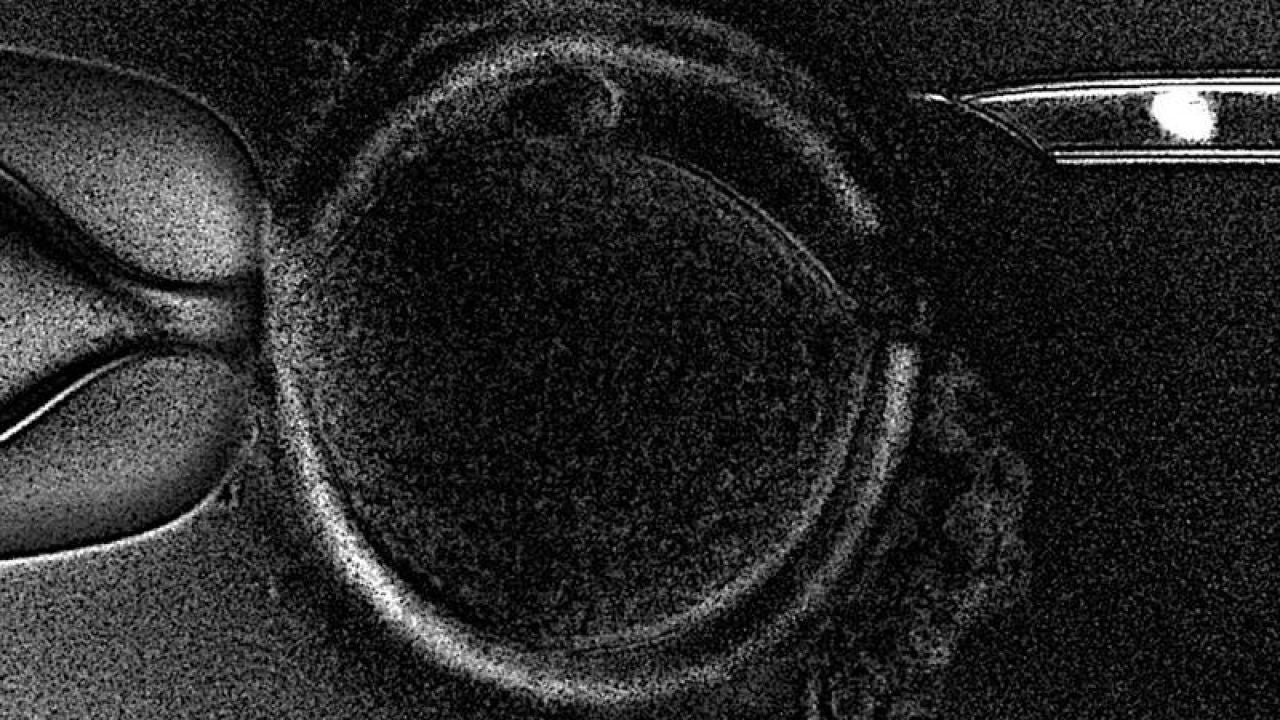

Técnica de la Transferencia de Huso MaternoEFE

"Esta técnica puede abrir una nueva era en la reproducción asistida", declaró el director científico de Embryotools, que tiene su sede en Barcelona, Nuno Costa-Borges, desplazado a Atenas para atender el parto. La novedad de la técnica de la Transferencia de Huso Materno (MST, en sus siglas en inglés) es que permite que mujeres que no consiguen el embarazo con tratamientos in vitro convencionales -que usan el material ovárico de la paciente-, puedan hacerlo con la ayuda de una donante de óvulos pero sin renunciar al propio material genético. Esto es posible porque se extrae el huso meiótico (núcleo) de un ovocito (óvulo inmaduro) no fecundado de la paciente, dónde se encuentra el ADN, y se implanta en un ovocito sano proveniente de una donante, al cual a su vez se ha retirado previamente su núcleo.

De esta forma, el óvulo resultante contiene el material genético de la paciente pero el resto de componentes, que tienen un papel crucial en la salida adelante del embrión, son de una donante sana. Este óvulo es, finalmente, fecundado con el esperma de la pareja e implantado en la paciente. Costa-Borges explicó que el nacimiento del primer bebé es "la última prueba que quedaba" para demostrar que se trata de "una técnica segura y eficiente", investigada durante más de cinco años por el equipo de Embryotools, y que les valió un premio de la Sociedad Americana de Medicina Reproductiva (ASRM).